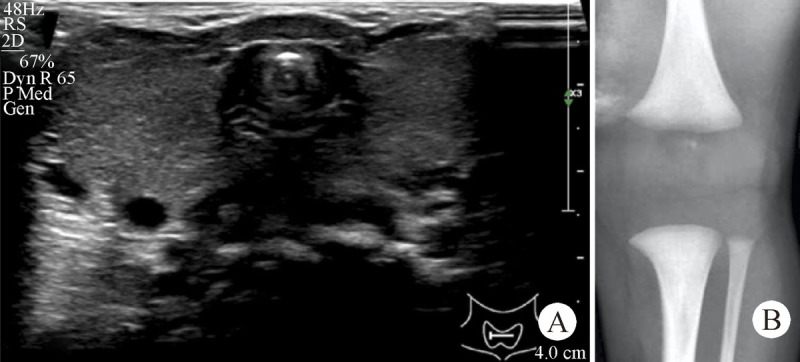

With the advances in fetal medicine, there will be more cases of congenital hypothyroidism (CH) diagnosed in the fetal period. However, there is no consensus on the management protocol. We present a successful case of conservatively managed fetal goitrous hypothyroidism due to compound heterozygous TG mutations. Goiter was observed in a fetus at 23 weeks of gestation. Because there was no evidence of transplacental passage of antithyroid antibody and drugs, iodine overload, and iodine deficiency, the fetus was highly suspected to have CH. Considering the potential risks of amniocentesis/cordocentesis, and lack of available parenteral levothyroxine in China, the fetus was closely monitored thereafter. A male neonate was delivered vaginally without complications at 39 weeks of gestation. We verified severe hypothyroidism in the infant and immediately initiated levothyroxine therapy. His growth and mental development were normal at the age of 8 month. Whole-exome sequencing showed that the neonate had two compound heterozygous mutations in the TG gene. We also performed a literature review of the prognosis of postnatal treatment of CH due to TG mutations and the result showed that postnatal treatment of CH due to TG mutations has a favorable prognosis. However, further prospective studies are warranted to verify this conclusion.

Abstract Image